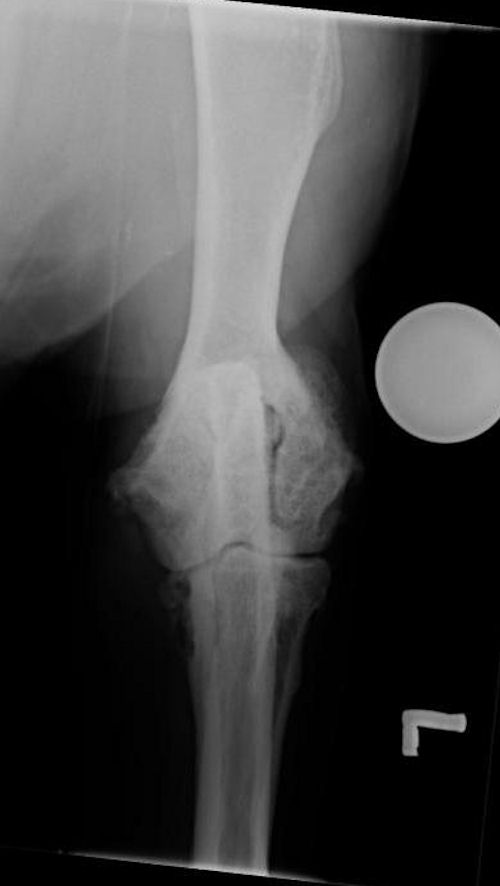

Canine Elbow. Moderate OA. Craniocaudal view Case Gallery Elbow Arthritis Dog Radiograph Typical radiographic findings include a slightly irregular radiolucent line in the metaphysis, running roughly parallel to the growth plate. Lateral radiograph of a young dog with elbow pain and lameness. Ced is the most common developmental disorder of the elbow joint in dogs. Radiographic features of canine elbow dysplasia. Notice the shape of the medial coronoid process (line), which is. Elbow Arthritis Dog Radiograph.